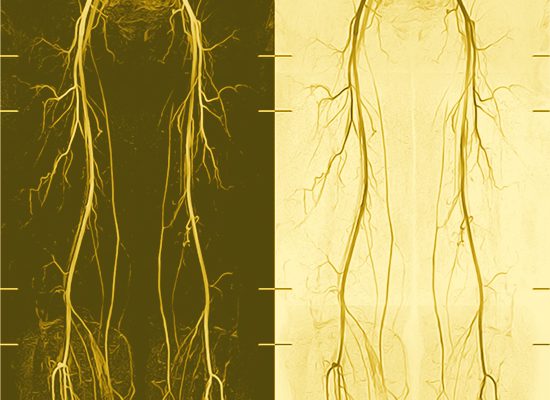

003 non CE BBA

4D Contrast Enhanced MR-Angio mit mDixon und Compressed SENSE